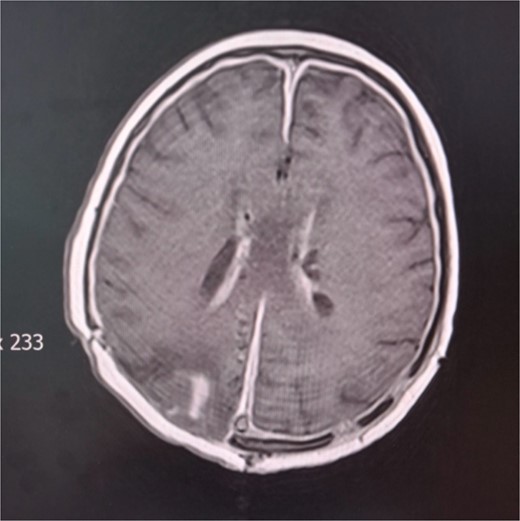

During the hospital stay, the valve became blocked, so another revision was done by inserting a new valve. The next day, re-occlusion of the valve occurred. Consequently, the whole external drainage system was removed. An external drain without a pressure valve was inserted in the right ventricle’s ventral horn. The patient started to develop symptoms of increased intracranial pressure, nausea, and vomiting. A control cerebral CT scan showed unilateral hydrocephalus; therefore, in the ventral horn of the left lateral ventricle, a second external drain without a valve was inserted. The patient started to become febrile with peaks of temperature to 38.5°C. T1-weighted gadolinium-enhanced MRI studies revealed ventriculitis (Fig. 4). Intraventricular colistin sulfate was added to the antibiotic treatment at 200.000 IU daily in each ventricle for 2 weeks. The ventricular drainage device was closed for 30 min after the injection of the antibiotic. In several instances, cerebrospinal fluid was collected from external drains for cytological and microbiological evaluation during this period. Cytological parameters tended to decrease until the normalization of the elements. On five different occasions, cerebrospinal fluid cultures were sterile. She was discharged from our clinic in stable general and neurological condition, afebrile and conscious. The patient is currently undergoing proton radiation therapy in a hospital abroad.

Cerebral MRI. Axial T1 weighted MRI showing ventriculitis with two external ventricular drainages (EVD) in the frontal horns of lateral ventricles.